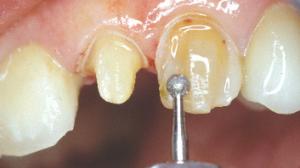

Préparation de la 23. Réalisation d'un sillon qui suit le périmètre de la face vestibulaire avec une fraise boule de 1mm.

La fraise boule est enfoncée à moitié. Ce sillon aura donc une profondeur d’environ 0,5 mm. Au collet, le sillon est pour le moment nettement éloigné de la gencive.

Des tranchées verticales sont réalisées avec la même fraise boule et à la même profondeur que le premier sillon (0,5mm).